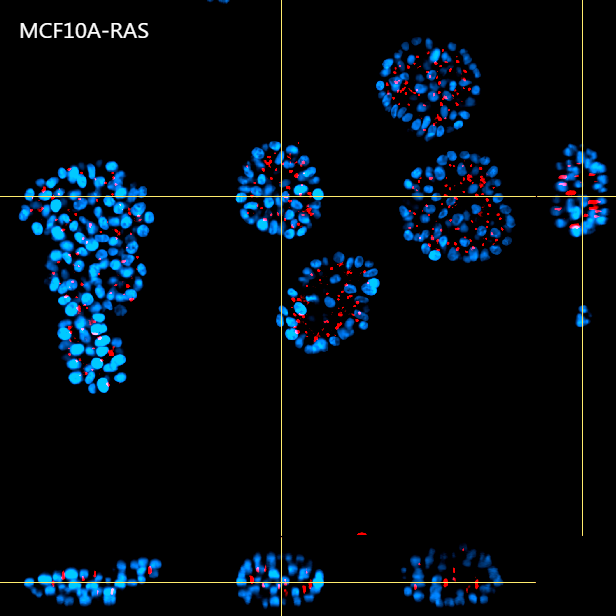

Figure 4 shows a maximum intensity projection (MIP) of 60 um Z-stack of non-malignant (A) and tumorigenic (B) acini. By providing homogeneous illumination over the entire 25 mm field of view (FOV), the X-Light V3 confocal spinning disk allowed us to analyze a large number of acini, reducing the number of images required to obtain robust data and, therefore, minimizing acquisition time.

A

B

Figure 4: MIP from 60 um Z-stack of non-malignant (A) and tumorigenic acini (B). Cells were cultured in 3D Matrigel suspensions and stained with pericentrin (red) and DAPI (blue). These images were acquired with a CFI Plan Apochromat Lambda D 20x air objective (20x, Nikon, 0.8 NA and 0.8 mm WD).

Using such an automated analysis pipeline, we have collected a wide range of information useful in understanding how mutated Ras receptors affect the proliferation and morphology of acini. As shown in Figure 8A, acinar structures from cultures of non-malignant breast cancer typically have round symmetrical shapes. On the other hand, the acini from malignant breast cancer cultures cause a deformation in the 3D architecture which causes the shape of the acini to be more elongated and deconstructed. Notably, the spheroids derived from the MCF10A K-Ras engineered line has a significant volume increase compared to the control line (Figure 8B). In fact, the transforming contribution of the k-Ras oncogene correlates with the increase in the cellular proliferative rate, and this causes an increase in volume already after 6 days in culture.

A

B

Figure 8: Representative MCF10A-CTR and MCF10A-RAS acini (A) and volume analysis (um3) (B). Cells were cultured in 3D Matrigel suspensions and stained with pericentrin (red) and DAPI (blue). This image was acquired with a CFI Plan Apochromat Lambda D 20x air objective (20x, Nikon, 0.8 NA and 0.8 mm WD). Volume comparison between MCF10A-CTR and MCF10A-RAS acini (B).